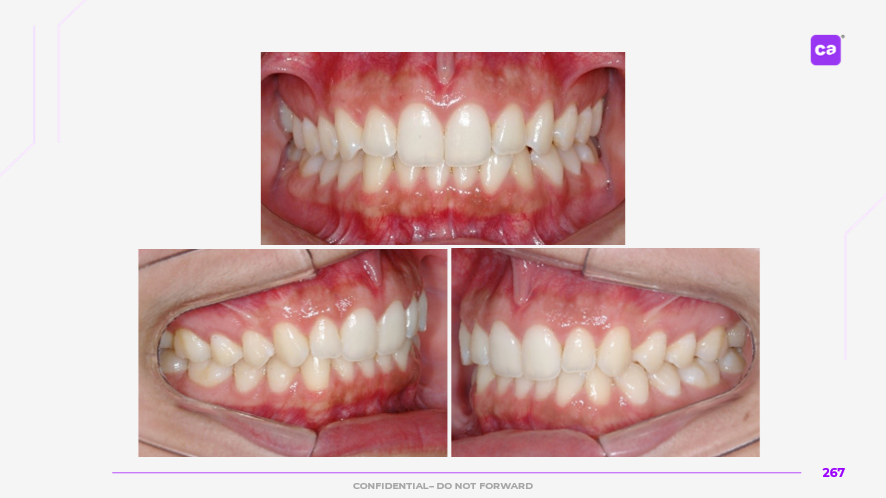

Figuras 3 – Fotos intraorais do caso clínico apresentadas em norma frontal e de perfil:

a) Condição inicial do caso clínico

b) Condição final do caso clínico

Na sequência apresentada, com os registros e comparação das fotos intraorais, observa-se a evolução do caso clínico desde a condição inicial até a finalização do tratamento com a conclusão do uso da série de alinhadores. Os resultados evidenciam a previsibilidade e acurácia do tratamento real em comparação às simulações e ao planejamento virtual inicial.

Observa-se a correção da sobremordida (mordida profunda), com avanço e torque vestibular dos incisivos superiores, juntamente com o nivelamento e alinhamento dentário das arcadas superior e inferior.

Além disso, nota-se o ajuste da linha média dentária superior, garantindo sua coincidência com a linha média inferior, bem como a otimização da curva e da estética do sorriso.